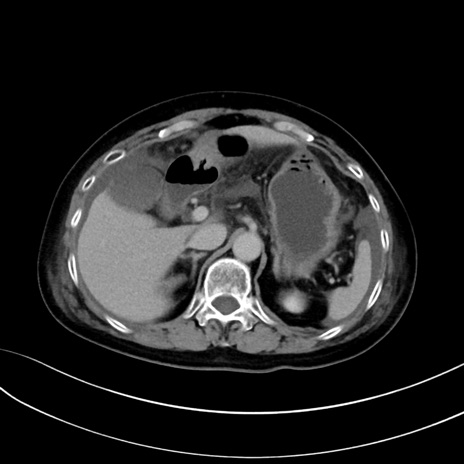

症例13 CT(横断像)1日半後